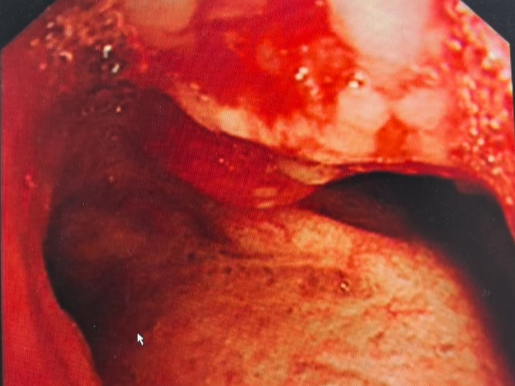

入院时,王大爷已经面色青紫、呼吸艰难、三凹征明显,支气管镜下探查及活检结果显示,主气道重度狭窄且病变累及右侧主干,伴原发性肺鳞癌。